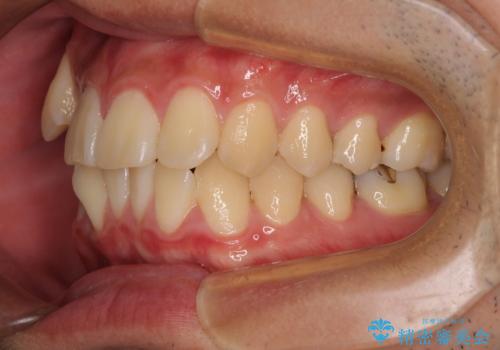

1年強でワイヤー装置を外すことができ、思ったよりも短期間で終了したため、患者様には大変喜んでいただきました。

口元が突出する仕上がりとならないように、舌突出癖改善のトレーニングをしっかりと行っていただきながら、矯正治療を進めていくこととしました。